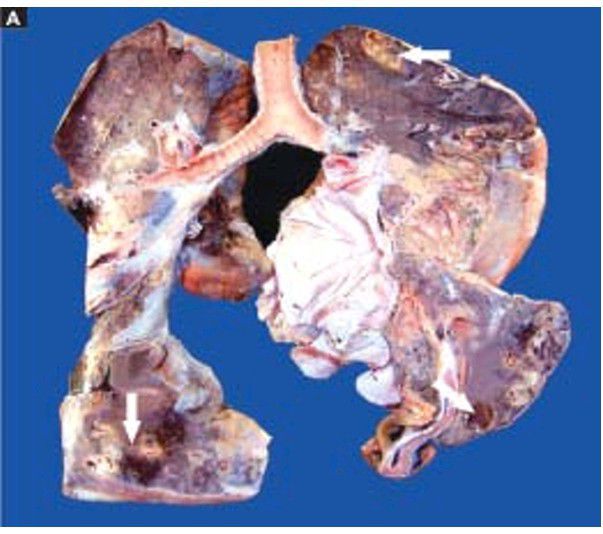

Lung abscess

The pleura is thickened. Cut surface of the lung shows multiple cavities 1-4 cm in diameter, having irregular and ragged inner walls (arrow). The lumina contain necrotic debris. The surrounding lung parenchyma is consolidated.